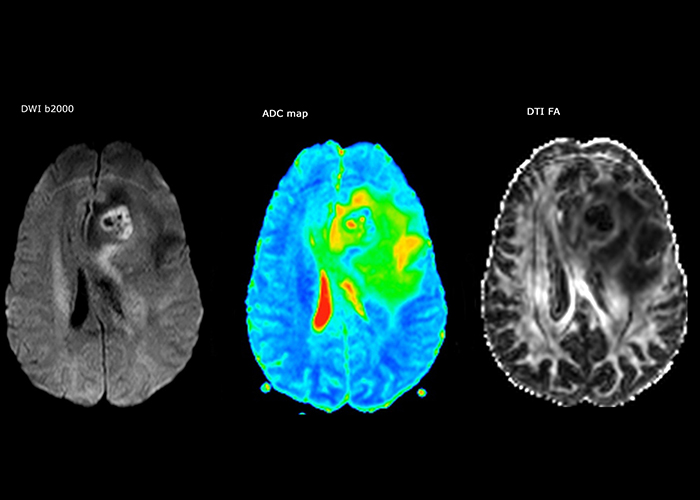

“The biggest challenges are properly characterizing the lesion and giving the surgeon all the information needed, such as the location of vessels and functional areas. Sometimes a very comprehensive exam is necessary, such as when a mass has been discovered at another hospital after which the patient is referred to us. We then do both lesion characterization and preoperative imaging in one exam, so both morphologic and functional assessment. For morphologic assessment we will use pre- and post-contrast T1-weighted imaging, FLAIR to assess infiltration, and diffusion. For functional characterization we will perform perfusion, spectroscopy, and susceptibility weighted imaging to look for micro vessels or micro hemorrhage inside the lesion[4]. For preoperative imaging we perform specific morphologic imaging that is compatible with the navigation system; depending on the location of the tumor, we would do fMRI or DTI.”

“Every center is different, but for me the ideal protocol for stroke includes diffusion weighted imaging, FLAIR, and fast susceptibility imaging,” says Dr. Savatovsky. “Our fast susceptibility weighted imaging takes 50 seconds, so it’s as fast as T2*-weighted imaging. It visualizes hemorrhage but also the clots. We also do 3D MR angiography that provides information on cervical and brain vessels. If the patient does not need immediate treatment, or if additional information is needed to decide on treatment, we might also add perfusion imaging and post-contrast T1-weighted imaging.”